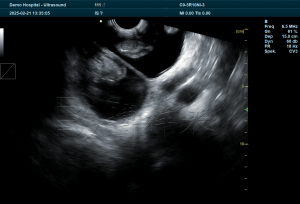

使用羊用B超机进行妊娠和多胎检测,是通过成像区显示子宫内的 胎囊数量 和 胎体结构 来判断的。孕羊的子宫双角结构让影像判断更具特点:多胎通常表现为多个胎囊同时出现在不同的子宫角区域。

在妊娠 28–45 天的黄金检测期内,影像中可以看到:

- 独立的多个胎囊

- 胎囊间的分隔反射

- 胎头、胎体的活动

- 胎心搏动等微小动态回声

使用专业的羊用B超机时,这些影像能以较高分辨率呈现,让技术员在短时间内判断胎数,误差率远低于传统触诊或经验估算。